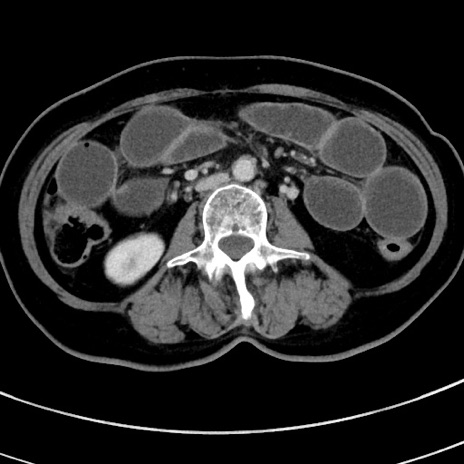

冠状断像

【症例】 60歳代女性

【主訴】むかつき、みぞおちの痛み

【現病歴】3日前よりむかつきがあり、食事がとれない。

【既往歴】糖尿病

【身体所見】発熱なし、心窩部圧痛軽度あるも、腹膜刺激症状なし。

【データ】WBC 7400、CRP 1.92